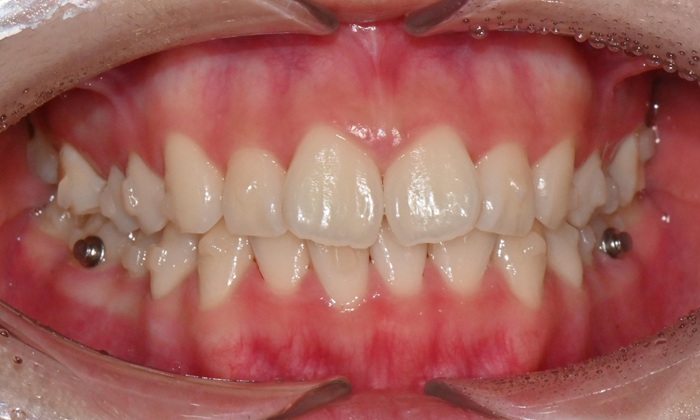

2025.3. 초진 (앞니 경미한 총생과 과개교합) - 연세정원치과

정밀진단 결과 위아래 앞니가 약간 겹쳐 있어 배열이 고르지 않은 상태였으며, 약간의 과개교합이 동반된 상태였습니다. 다만 골격적인 문제나 안모 불균형은 없었고, 측면에서도 돌출감 없이 비교적 안정적인 안모를 유지하고 있었습니다.

이러한 점을 종합적으로 고려해보았을 때 치아 배열의 개선과 교합 조정을 중심으로 한 비발치 교정 치료가 적합한 케이스였습니다. 또한 환자가 고등학생이라는 점, 그리고 학업과 일상 생활에 대한 부담을 최소화하고 싶다는 보호자의 의견을 반영하여, 인비절라인으로 선택하게 되었습니다.